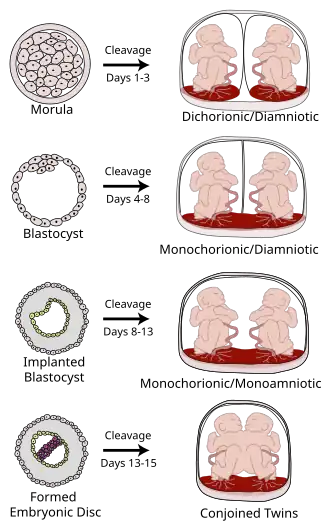

Various types of chorionicity and amniosity (how the baby's sac looks) in monozygotic (identical) twins as a result of when the fertilized egg divides.

Monochorionic twins are monozygotic (identical) twins that share the same placenta. If the placenta is shared by more than two twins (see multiple birth), these are monochorionic multiples. Monochorionic twins occur in 0.3% of all pregnancies.[1] Seventy-five percent of monozygotic twin pregnancies are monochorionic; the remaining 25% are dichorionic diamniotic.[2] If the placenta divides, this takes place before the third day after fertilization.[2]

Monochorionic twins generally have two amniotic sacs (called Monochorionic-Diamniotic "MoDi"), but sometimes, in the case of monoamniotic twins (Monochorionic-Monoamniotic "MoMo"), they also share the same amniotic sac. Monoamniotic twins occur when the split takes place after the ninth day after fertilization.[2] Monoamniotic twins are always monozygotic (identical twins).[3] Monochorionic-Diamniotic twins are always monozygotic.